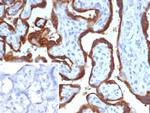

HCG-beta (Pregnancy and Choriocarcinoma Marker) Antibody in Immunohistochemistry (Paraffin) (IHC (P))

HCG-beta (Pregnancy and Choriocarcinoma Marker) Antibody (1081-MSM15-P1ABX) in IHC (P)

Formalin-fixed, paraffin-embedded human placenta stained with HCG-beta Mouse Monoclonal Antibody (hCGa/7875). Inset: PBS instead of primary antibody; secondary only negative control. {{ $ctrl.currentElement.advancedVerification.fullName }} 验证信息 View more